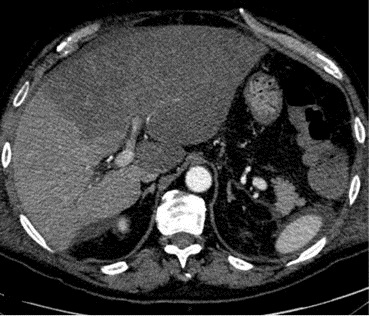

Image TDM de hepatite

: Aspect radiologique de

heaptite aigue du foie le plus souvent est image de

hepatomegalie : Depasse 15,5cm au line medio-clavuculaire

droit .Image de hypodense parenchymateuse . Image de oedeme

periportale ( aspect hypodensse peri portale ) .

Lymphadenopathie periportale et hepato-duoenale .

Aspect TDM de hepatite aigue

est image de hypoechogene dela parenchyme du foie ,

image de epaissisement de la paroi de la vesicule

biliaire . Coupe TDM axiale du foie |

Hepatite aigue : Aspect de

hypodense region perioportale et peri hillaire du

foie ( >5mm ) . Image de hypodense de la parenchyme

du foie . Lymphadenopathie hillare dans ce cas est

en bien se voyait . Image radiologique du foie

en coupe TDM axiale . |

Aspect hypodense du

parenchyme du foie dansd hepatite aigue . Le

foie est en moins densite que la rate . Et image de

hypodense region periportale et image de

adenopâthie hileire du foie . |